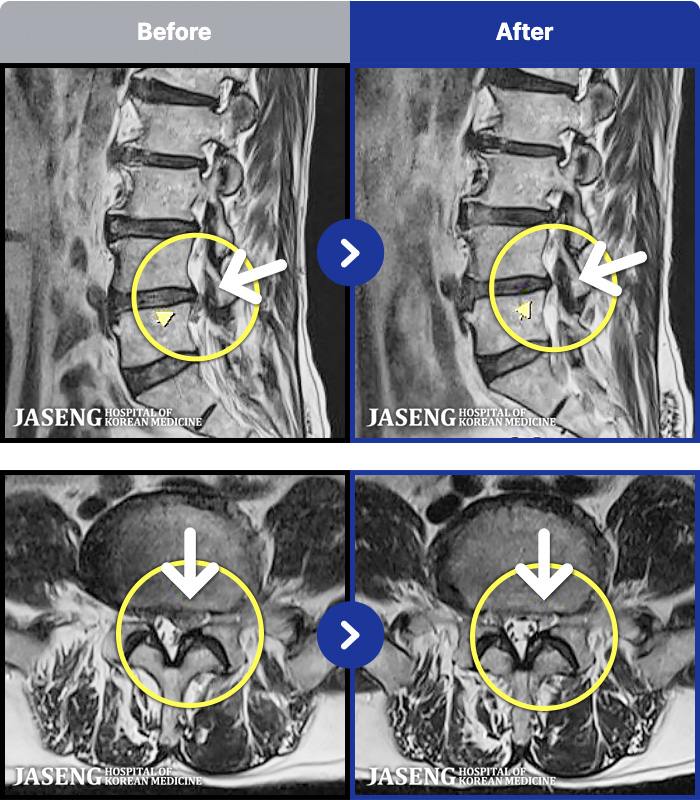

MRI ġ

1,299 MRI ũ ʸ Ȯϼ.